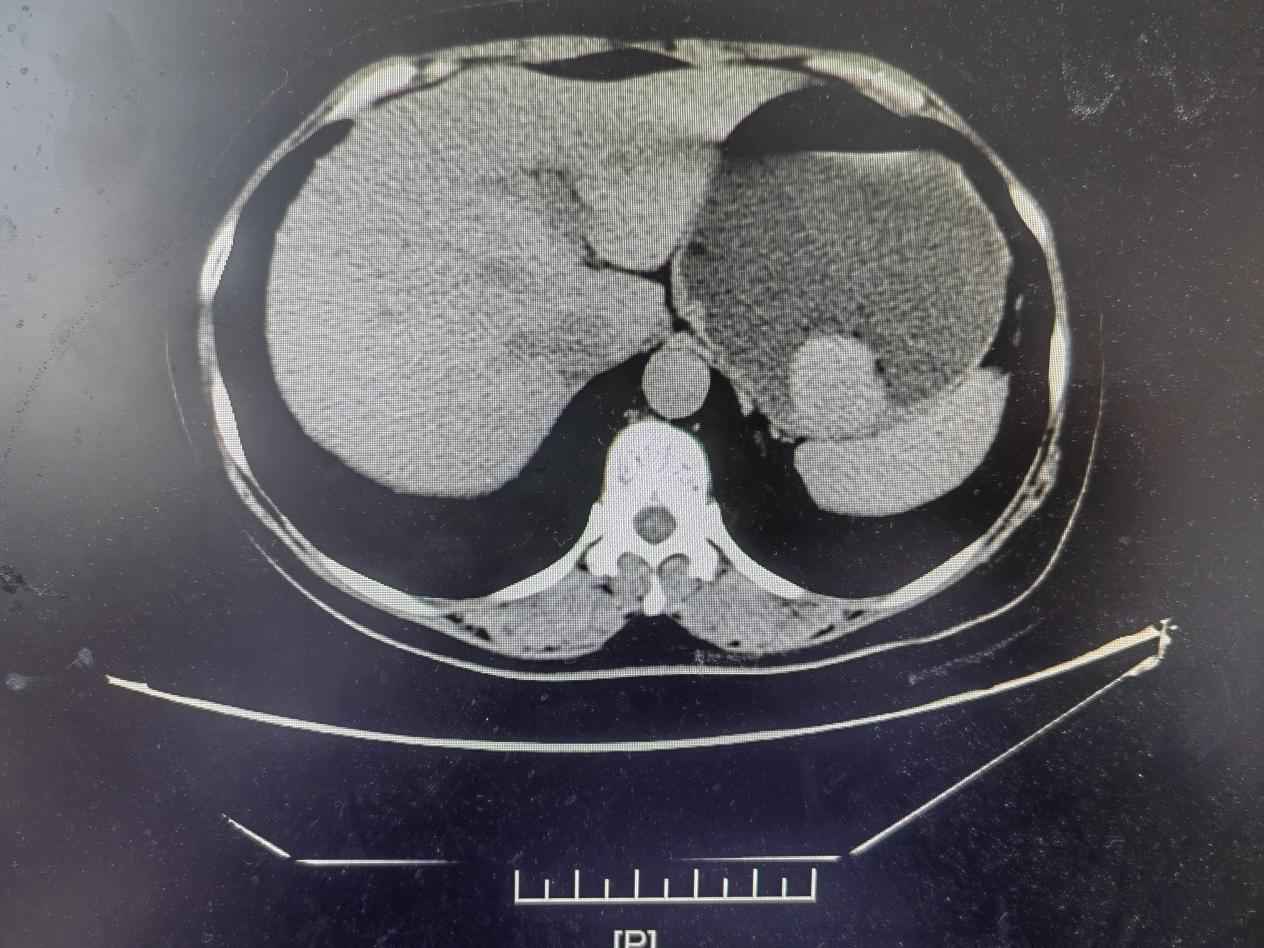

患者,女性,45岁,系因反复上腹部不适10月,我院胃镜检查提示胃底隆起性病灶入住普通外科,术前CT提示间质瘤。既往2月前因子宫肌瘤在外院开腹大切口行子宫切除。术后患者疼痛感明显,故患者要求微创治疗。经科室讨论后为患者行全腔镜下胃间质瘤切除术。手术顺利,术后恢复良好。

术前图片